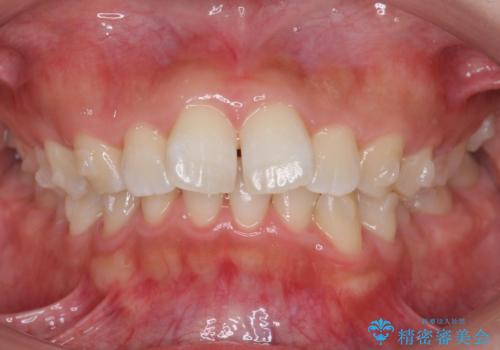

出っ歯の治療 抜かずに 短期間で目立たない治療

- 前歯のがたつきと突出を主訴に来院。

歯を抜かずに非抜歯で治療しました。

治療にも大変満足していただきました。

リファインメントも1回で済んでいます。